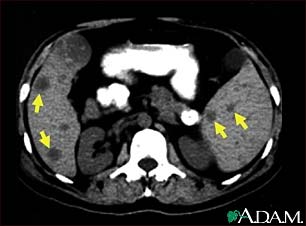

Spleen metastasis - CT scan

This CT scan of the upper abdomen shows multiple tumors in the liver and spleen that have spread (metastasized) from an original intestinal cancer (carcinoma).